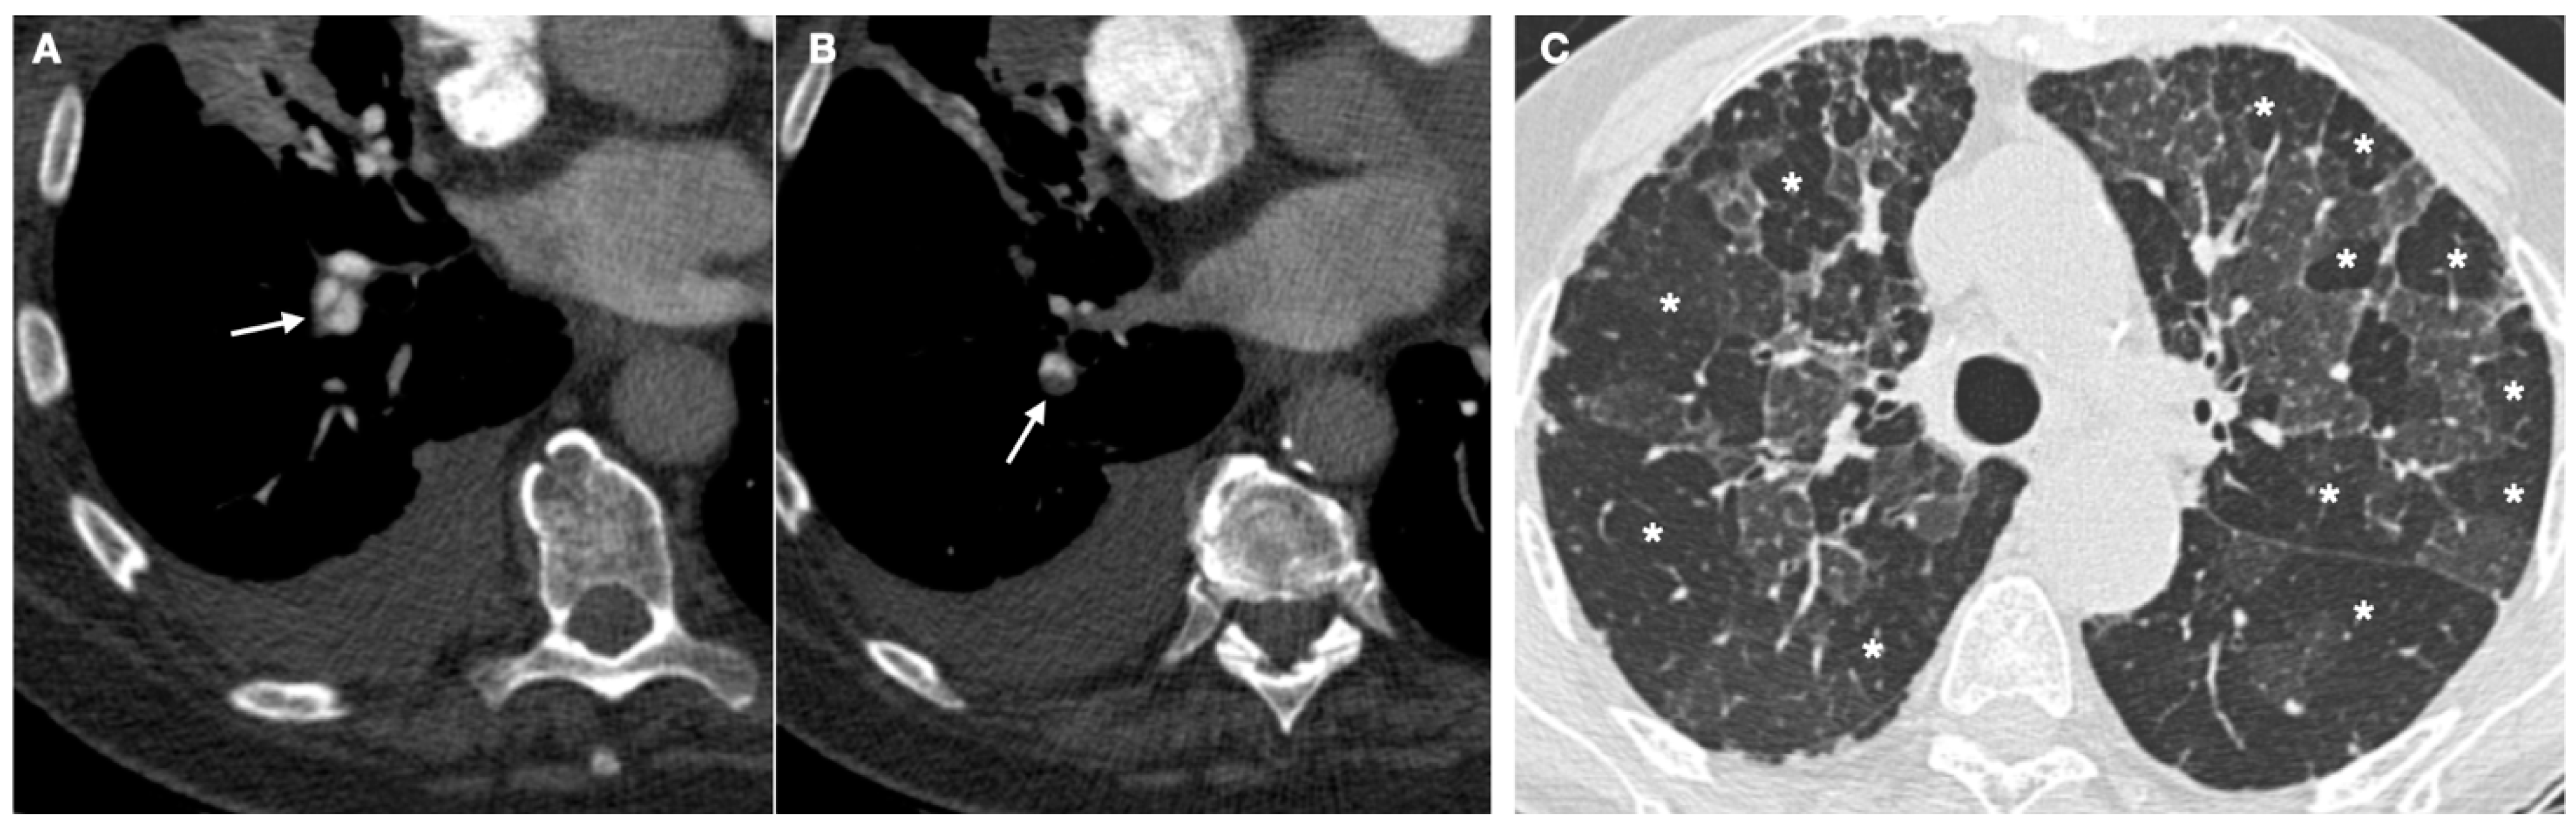

- Sherrick, A.D.; Swensen, S.J.; E Hartman, T. Mosaic pattern of lung attenuation on CT scans: Frequency among patients with pulmonary artery hypertension of different causes. Am. J. Roentgenol. 1997, 169, 79–82. [Google Scholar] [CrossRef] [PubMed] [Green Version]